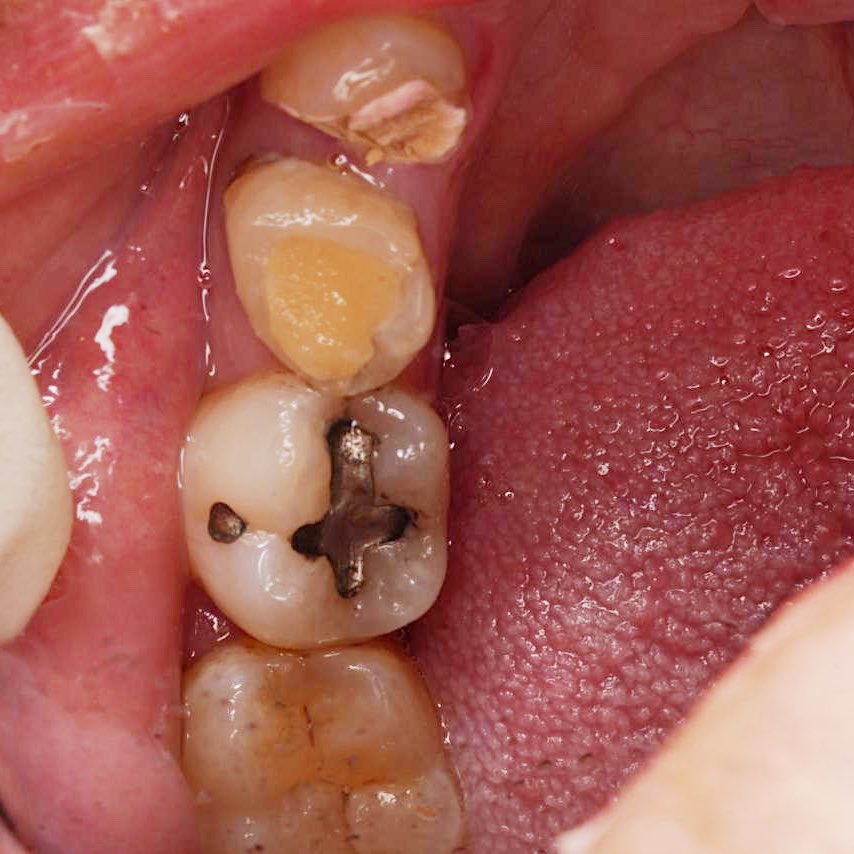

Successfully completed endodontic treatment on #36 with Radix Entomolaris, a challenging and rewarding case ✨

Grateful to have performed it under the supervision of @DrKhawlahSays and @HananShu

Thank you for your guidance and continuous support in advancing our clinical skills.